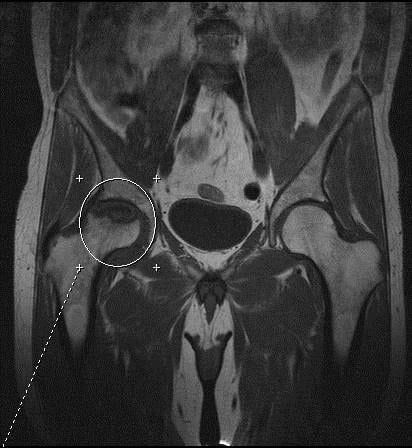

С помощью магнитно-резонансной томографии выявляют патологические изменения в костях, суставных хрящах, сумке, связках, нервах, сосудах и периартикулярных тканях. При правильной интерпретации исследование позволяет поставить диагноз без каких-либо дополнительных диагностических мероприятий. Давайте посмотрим, что показывает томография тазобедренных суставов при разных заболеваниях.

Пациенты, которым был установлен эндопротез ТБС диаметром более 35 мм с парой трения «металл-металл», нуждаются в тщательном ежегодном мониторинге на протяжении первых 5 лет. Проведение МРТ позволяет выявить патологические изменения в перипротезных мягких тканях и костях. Они указывают на высокий риск развития остеолиза, нестабильности эндопротеза и инфекционных осложнений.

| Асептический некроз головки бедренной кости | На первой стадии болезни в головке бедренной кости выявляют локальный гиподенсивный участок с возможной каемкой умеренного склероза. На следующих стадиях на МРТ-граммах появляются некротические дефекты, участки секвестрации, кисты и т.д. Асептический некроз ІІ-V стадии можно диагностировать даже с помощью рентгенографии |